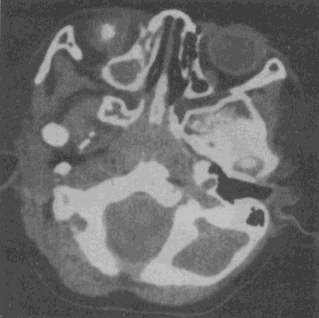

女性,14个月。发现视力低下CT如图所示,最可能的诊断是 YZ332_1_46_17.gif YZ332_1_46_17_1.gif

• A.脉络膜黑色素瘤

• B.视神经胶质瘤

• C.海绵状血管瘤

• D.视网膜母细胞瘤

• E.眼底出血